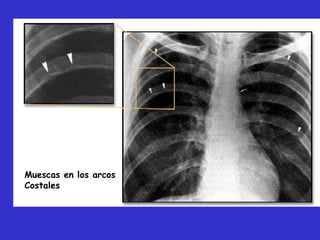

esofagrama, 3 invertido. Muescas en los

arcos costales.

Muescas en los arcos

Costales